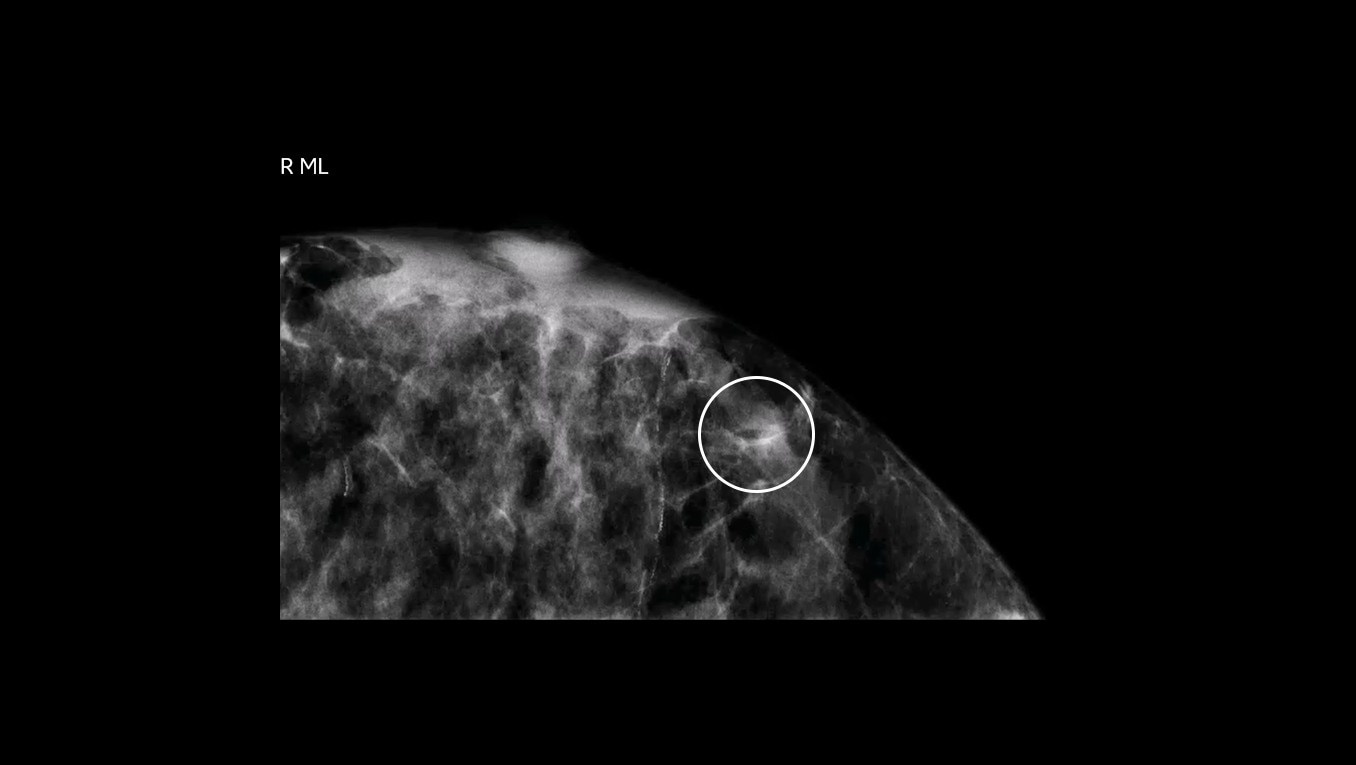

Fast procedure

CEM biopsy can be done within 15 minutes1.

Switch to interventional on the same system within your current room in 2 minutes4.